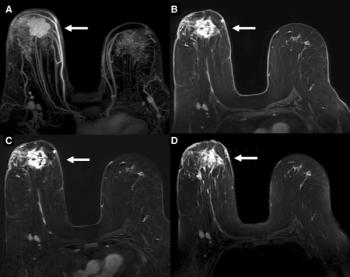

Existing protocol to re-assess women after six months is appropriate; imaging can identify cancers that have spread to lymph nodes.